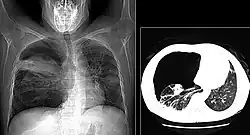

The diagnosis can be confirmed by the characteristic appearance of the chest X-ray and an arterial oxygen level (PaO2) that is strikingly lower than would be expected from symptoms. Gallium 67 scans are also useful in the diagnosis. They are abnormal in about 90% of cases and are often positive before the chest X-ray becomes abnormal. Chest X-ray typically shows widespread pulmonary infiltrates. CT scan may show pulmonary cysts (not to be confused with the cyst-forms of the pathogen).

These chest radiographs are of two patients. Both show ground glass opacities. The left X-ray shows a much more subtle ground-glass appearance while the right X-ray shows a much more gross ground-glass appearance mimicking pulmonary edema.[7] -

High-resolution computed tomography (HRCT) showing ground-glass attenuation with a geographic or mosaic distribution.[7] -

HRCT of cysts of pneumocystis pneumonia. These are usually multiple and bilateral, but range in size, shape and distribution.[7]